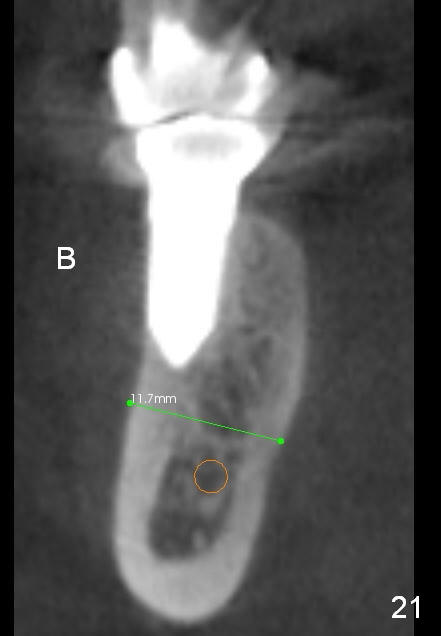

CBCT taken 15 months post cementation shows that the implant is buccally placed (Fig.21 B), associated with possible postop buccal plate resorption (as compared to Fig.23 (coronal section of the site of #19). The buccal plate is not only thinner than the lingual one, but also concave (Fig.22 <). The tooth center (i.e., septum; Fig.23 T) is more buccally located than the center of the basal bone (B). Considering the denser bone lingually, the initial osteotomy should be more lingually (^). If the implant develops infection, it will be replaced by a more lingually placed implant (Fig.24 green).